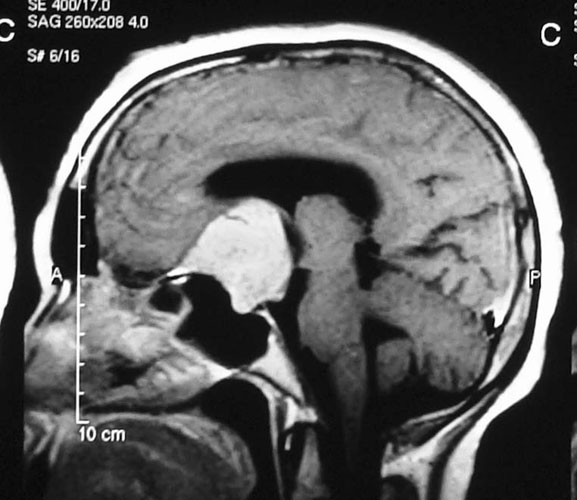

Craniopharyngioma

Craniopharyngioma is a common tumor in childhood, but can also be seen in adults. These tumors often present with endocrine problems, abnormalities of appetite, visual problems. MRI gives diagnosis and treatment involves surgery. Attempt must be made at complete excision, with safeguarding of vital hypothalamic functions. Radiation may be required after surgery to halt tumor followed by surgical excision, with excellent results.